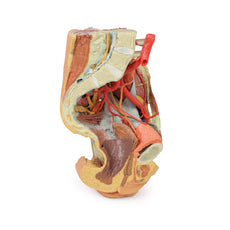

The umbilical and lumbar regions

Most of the organs occupying the umbilical and lumbar regions of the abdomen

have been removed in order to expose structures in the posterior abdominal wall. In the midline, the descending

abdominal aorta and inferior vena cava dominate the region, with the testicular arteries and veins isolated and

traceable towards the inguinal regions. Two right lumbar arteries are visible arising from the aorta, and

despite removal of the mesenteries and most of the colon the inferior mesenteric artery can be seen giving rise

to the left colic, sigmoid and superior rectal arteries. On the right side of the specimen inferior to the

kidney, the subcostal, iliohypogastric and ilioingual nerves are exposed alongside the circumflex iliac artery.

The hypogastrium and iliac regions

In the midline, the bifurcation of the descending abdominal aorta into the

common iliacs (and subsequent division into the internal and external iliacs) can be observed deep to some of

the overlying structures (e.g., testicular vessels, ureters) noted previously. On the right side, the obturator

artery can be seen traversing from its origin towards the anterior aspect of the pelvis. The mirrored merging of

external, internal and common iliac veins into the inferior vena cava is also preserved. Within the confines of

The thigh

Anterior dissections into the femoral triangle region have been undertaken to both thighs with

varying preservation of contents. On the right side the femoral sheath has been removed to expose the femoral

artery, vein and the deep inguinal lymph nodes. The femoral artery has been sectioned with a portion removed to

expose the origin of the profunda femoris and to better appreciate the draining of the great saphenous vein into

the femoral vein. Just lateral to these structures the very terminal component of the femoral nerve is visible.

On the left side a slightly larger dissection window has been opened to expose more of the underlying anterior

and medial thigh compartment muscles, from the sartorius and iliopsoas laterally to the pectineus and adductor

longus medially. The femoral artery has been preserved, with a well-preserved superficial circumflex iliac

artery and the origin of the profunda femoris visible adjacent to the femoral nerve.

The model terminates at

the level of the mid-thigh, and while not a primary focus of the model the spatial organisation of structures in

the cross-section can be seen. This includes the anteriorly positioned femoral diaphysis with tightly-packed

anterior compartment muscles and the passage of the femoral artery and vein in the subsartorial canal.